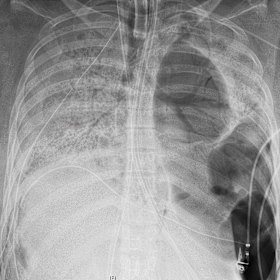

The patient's chest X-ray before she received a new set of lungs. Northwestern Medicine

The patient, who is in her 20s, was on a ventilator and heart-lung machine for almost two months before her operation last Friday at Northwestern Memorial Hospital.

The 10-hour procedure was challenging because the virus had left her lungs full of holes and almost fused to the chest wall, Dr Ankit Bharat, who performed the operation, said.